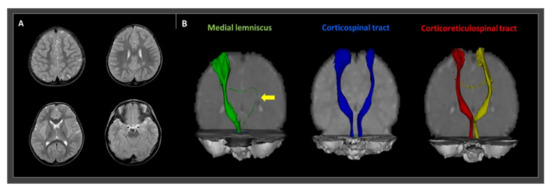

The Oxford Center for Functional Magnetic Resonance Image of the Brain (FMRIB) Software Library (FSL; http://www.fmrib.ox.ac.uk/fsl) was used to analyze the diffusion-weighted imaging data. Fiber tracking was performed using a probabilistic tractography method based on a multi-fiber model, applied using tractography routines implemented in FMRIB diffusion (5000 streamline samples, 0.5-mm step lengths, curvature thresholds = 0.2). The ML, corticospinal tract (CST), and corticoreticulospinal tract (CRT) were depicted by selecting fibers passing through both regions of interest (ROIs) [7,8]. For ML integrity analysis, the seed ROI was placed on the medial posterior region of the medullary pyramids and the target ROI was placed on the ventroposterolateral nucleus of the thalamus. A seed ROI of the CST was placed on the CST portion of the anterior mid-pons on a two-dimensional (2D) color map. For CST, the target ROI was located on the CST portion of the anterior lower pons, again on a 2D color map. To analyze the state of the CRT, a seed ROI was positioned on the reticular formation in the medulla. The first target ROI was positioned on the midbrain tegmentum, and the second was positioned on the primary motor cortex, specifically in Brodmann area 6. Fiber tracking of these three neural tracts was initiated at the center of the seed voxel with a fractional anisotropy >0.2 and ended at the voxel having a fiber assignment <0.2 and a tract-turning angle <60°. The integrity of the right ML was well-preserved, but the left ML was disrupted and significantly thinned. On the other hand, both the CST and CRT were well depicted without any significant disruption (Figure 1).

Figure 1. T2-weighted magnetic resonance imaging and diffusion tensor tractography (DTT) images of a 27-month old male cerebral palsied patient with gait instability. (A) T2-weighted magnetic resonance images show no abnormal lesions. (B) DTT revealing a thinned and disrupted left medial lemniscus (yellow arrow). However, the right medial lemniscus and both the corticospinal and corticoreticulospinal tract show preserved integrity to the cortex.